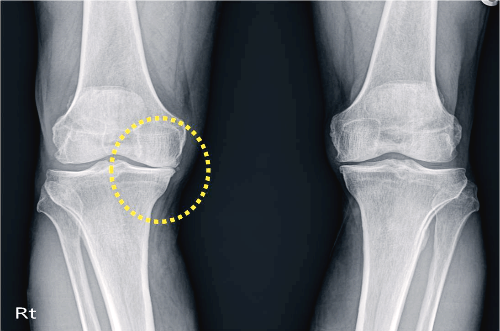

골관절염은 연골에 손상이 가해지면서 관절의 간격이 줄어들고 뼈가 서로 맞닿아 통증을 동반하는 질병입니다. 콘드로이친은 질병과 외부 충격으로부터 체내의 조직을 안전하게 보호하고 동시에 조직 표면에 가해지는 충격 등을 이겨낼 수 있도록 탄성을 주는 프로테오글리칸(Proteoglycan)이라는 물질의 생성을 돕게 됩니다. 때문에 콘드로이친은 특히 골관절염에 효과가 있습니다.

콘드로이틴황산염은 연골 구성 성분의 하나이고 연골세포를 자극해 연골조직을 정상적으로 복원하는데 효능이 있다고 알려져 있습니다. 특히 외부 자극에 의해 문제가 되는 TNF-알파 등 사이토카인의 작용을 억제하는 역할을 합니다. 그리고 지속적인 염증 유발 및 연골 파괴 유발 사이토카인을 감소시켜 관절 내 염증 및 통증반응 그리고 연골파괴를 막아주는데 도움을 줍니다.

그렇지만 이미 연골의 손상이 심각하다면 관절 영양제를 먹어도 손상된 연골을 복구할 수는 없습니다. 다만 관절의 손상 속도를 지연시키는 보조제 역할 정도로 활용할 수 있습니다.